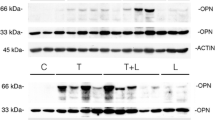

Runt-related transcription factor 2 (Runx2) mRNA expression was more predominant in the groups that received LLLT (groups 2 and 4) than in those that did not receive LLLT (groups 1 and 3) (Table 3 and Fig. 2). Figure 2a shows the means and standard deviations of the relative levels of runx2 mRNA expression on every experimental day in all the groups. The relative density of runx2 mRNA expression was significantly higher in group 2 than in group 1 at 3, 5, 7, and 14 days, and higher in group 4 than in group 3 at 5, 7, and 14 days (p < 0.05). At 7 days, the relative density differences were greatest between group 1 (52.8 ± 9.18) and group 2 (146.3 ±9.68) (a factor of 2.77) and between group 3 (40.3 ± 4.90) and group 4 (126.1 ± 7.68) (a factor of 3.13). At 5 and 14 days, the differences between groups 3 and 4 (2.72- and 1.93-fold, respectively) were greater than the differences between groups 1 and 2 (1.81- and 1.78-fold, respectively).

Relative densities of runx2 (a), collagen type I (b), and osteocalcin (c) mRNA expression of the tooth extraction sockets in normal (groups 1 and 2) and STZ-induced diabetic (groups 3 and 4) rats. Higher expression of runx2 and collagen type I mRNA in groups with LLLT than in those without LLLT demonstrated that LLLT has a promoting effect in the initial stages of healing. The level of osteocalcin mRNA expression increased more in the groups receiving LLLT than in the others except at day 3, and the difference increased with time to day 14. This means that LLLT was effective in promoting bone calcification. *: p < 0.05, statistically significant between groups 1 and 2, **: p < 0.05, statistically significant between groups 3 and 4

The expression of collagen type I mRNA was higher in group 2 than in group 1 over the whole experimental period, and higher in group 4 than group 3 at 5 and 7 days (Table 3 and Fig. 2). Groups 3 and 4 were similar at 3 and 14 days. Figure 2b shows the means and standard deviations of the relative densities of collagen type I mRNA expression on every experimental day in all the groups. With LLLT, the relative density of collagen type I mRNA expression had a tendency to increase until day 7 and then decrease by day 14. The largest difference in the relative density of collagen type I mRNA expression was observed at day 7 between group 1 (46.5 ± 0.8) and group 2 (118.0 ± 9.0), a 2.54-fold difference, and at day 5 between groups 3 (31.7 ± 3.1) and 4 (54.6 ± 5.6), a 1.72-fold difference.

Osteocalcin mRNA expression tended to increase until the end of the study period except for group 3. Osteocalcin mRNA was expressed more in the groups with LLLT than in those without LLLT except at day 3 in the diabetic rats (Table 3 and Fig. 2). Figure 2c shows the means and standard deviations of the relative densities of osteocalcin mRNA expression on every experimental day in all the groups. The relative density difference was greatest at day 14 between the group 1 (66.3 ± 5.25) and group 2 (169.5 ± 3.65), a 2.56-fold difference, and at day 7 between groups 3 (42.4 ± 0.95) and 4 (101.7 ± 7.87), a 2.40-fold difference.

RT-PCR analyses confirmed that bony healing was delayed in diabetic rats and that LLLT promoted bony healing in both normal and diabetic rats. Runx2 is a transcription factor that belongs to the runt-domain gene family [31]. It is the first marker of premature osteoblasts in the differentiation of osteoblasts, and is expressed in the initial period of bone formation [32]. Runx2 plays important roles in several steps of skeletal development by activating other genes involved in the formation of bone matrix [33]. The stimulation of runx2 expression by LLLT means that the differentiation of osteoblasts is stimulated, more osteoblasts perform their functions, and more new bone is formed. RT-PCR revealed significant differences in the relative density of runx2 mRNA in normal and diabetic rats, particularly at days 5, 7, and 14, depending on the presence of LLLT. Collagen type I is one of the major organic matrix components in the bone matrix and calcification occurs once collagen is formed [34]. The level of collagen type I mRNA expression was higher after LLLT and the difference increased to day 7, but decreased slightly by day 14 due to calcification. Runx2 and collagen type I are factors expressed in the early stage of bone healing. Therefore, the higher expression of runx2 and collagen type I mRNA in groups with LLLT than in those without LLLT demonstrated that LLLT has a promoting effect in the initial stages of healing. As bone calcification begins, osteocalcin, a marker of mature osteoblasts, is secreted from osteoblasts and increases only in the latter stages of osteoblast differentiation [35]. Osteocalcin is not easily detected in osteoid tissue before calcification and is generally detected during calcification by immunohistochemical staining [32]. The level of osteocalcin mRNA expression increased more in the groups receiving LLLT than in the others except at day 3, and the difference increased with time to day 14. This means that LLLT was effective in promoting bone calcification. Therefore, low-level diode laser irradiation had positive effects on extraction sockets after surface healing and influenced the calcification process because it could reach deeper tissues.